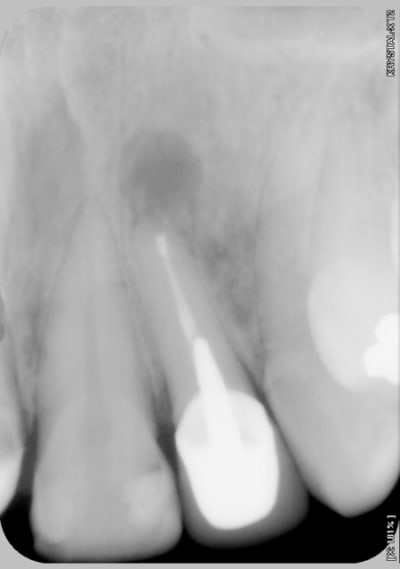

Il y a plusieurs trucs que je ne comprends pas dans ce raisonnement, si tu ne fais pas une incision intra-sulculaire c'est pour ne pas avoir de récession surtout sur ta ccm.

Hors, tu as un cas qui ne demande que ça. En effet il semble que les dents soient légèrement "impactées" et le ratio longueur/largeur est inesthétique, surtout avec un sourire gingivale.

De plus tu fais une résection sur une dent que tu as couronné il y a un an, je ne connais pas les antécédents de la dent mais avant ça, un retraitement était peut être envisageable, non ?

Je n'ai pas de photos du sourire, mais amha dans un cas similaire et si la demande esthétique est là, alors en fonction de la ligne du sourire et de l'émail recouvert j'aurais fait:

- rettt endo

- gingivectomie/ alongement de couronne -prov 22

- motivation/instruction hygiène

- et ccm si guerison.